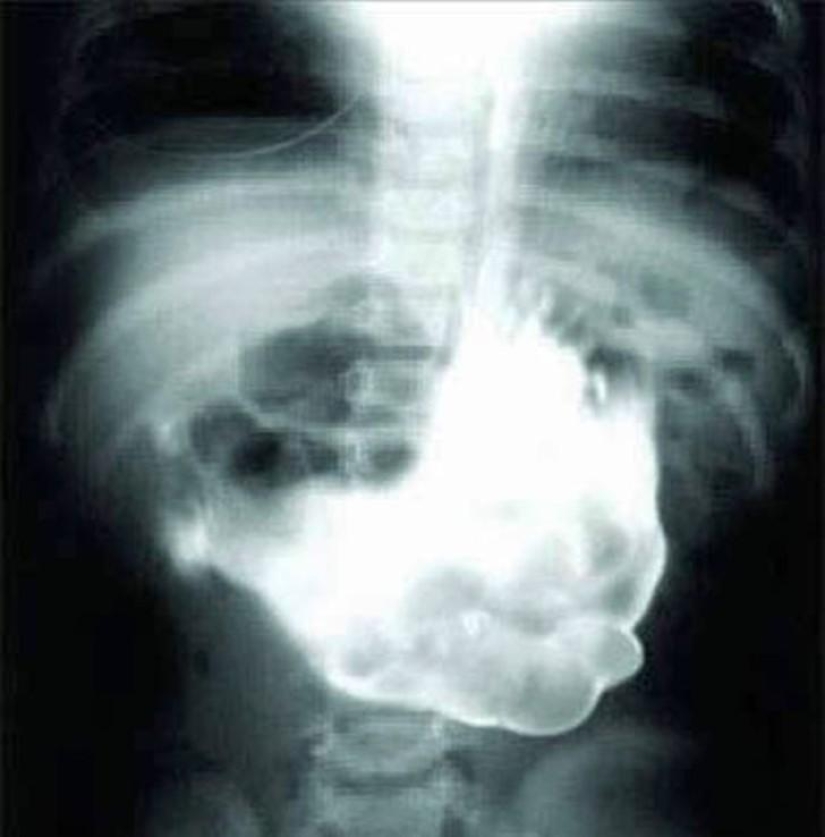

Enorme ovillo de lana.